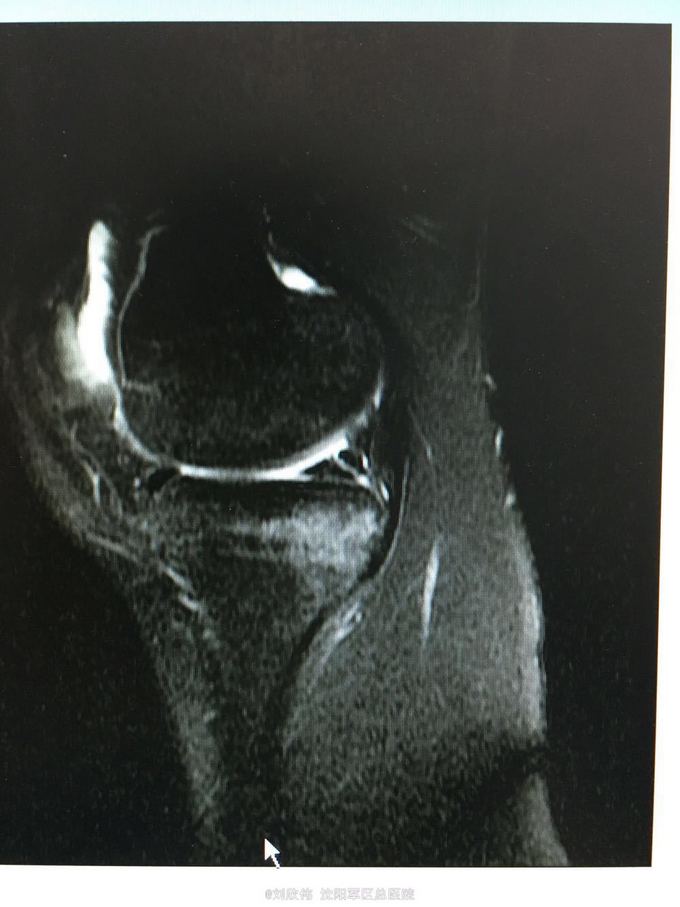

训练致右膝肿痛伴活动受限3个月 自觉脱臼感

右膝lachman试验,轴移试验阳性 MRI提示ACL已显示不清,半月板后角高信号(但术中未见撕裂,mri存在假阳性)

右膝前交叉韧带断裂 右膝半月板损伤 手术方法如题,直接上图